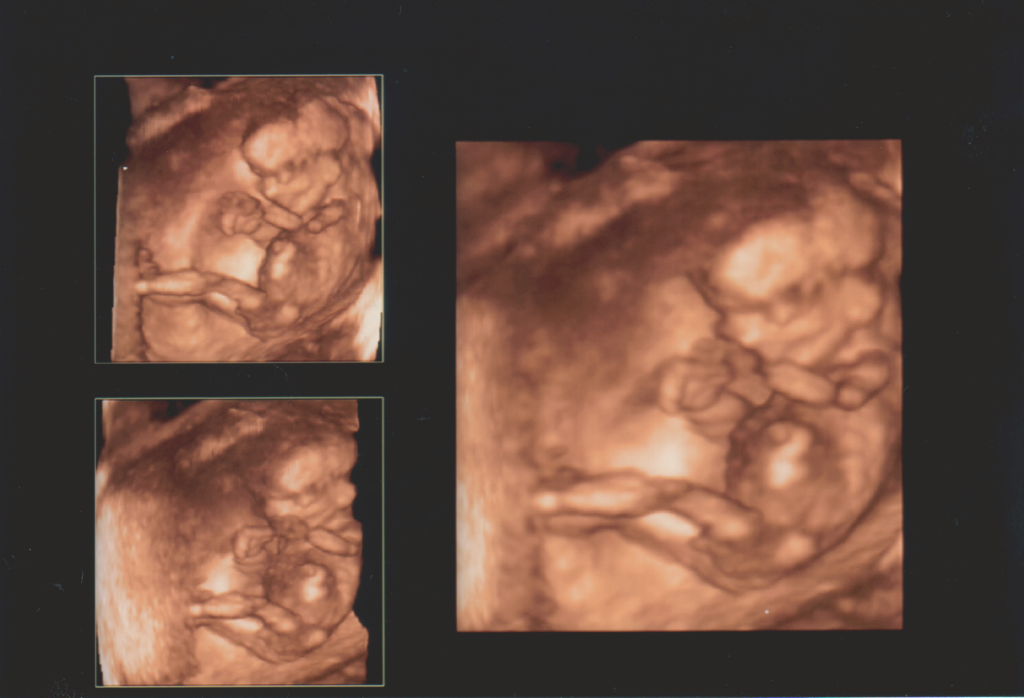

13. heti 4D ultrahang

Első baba mozi.